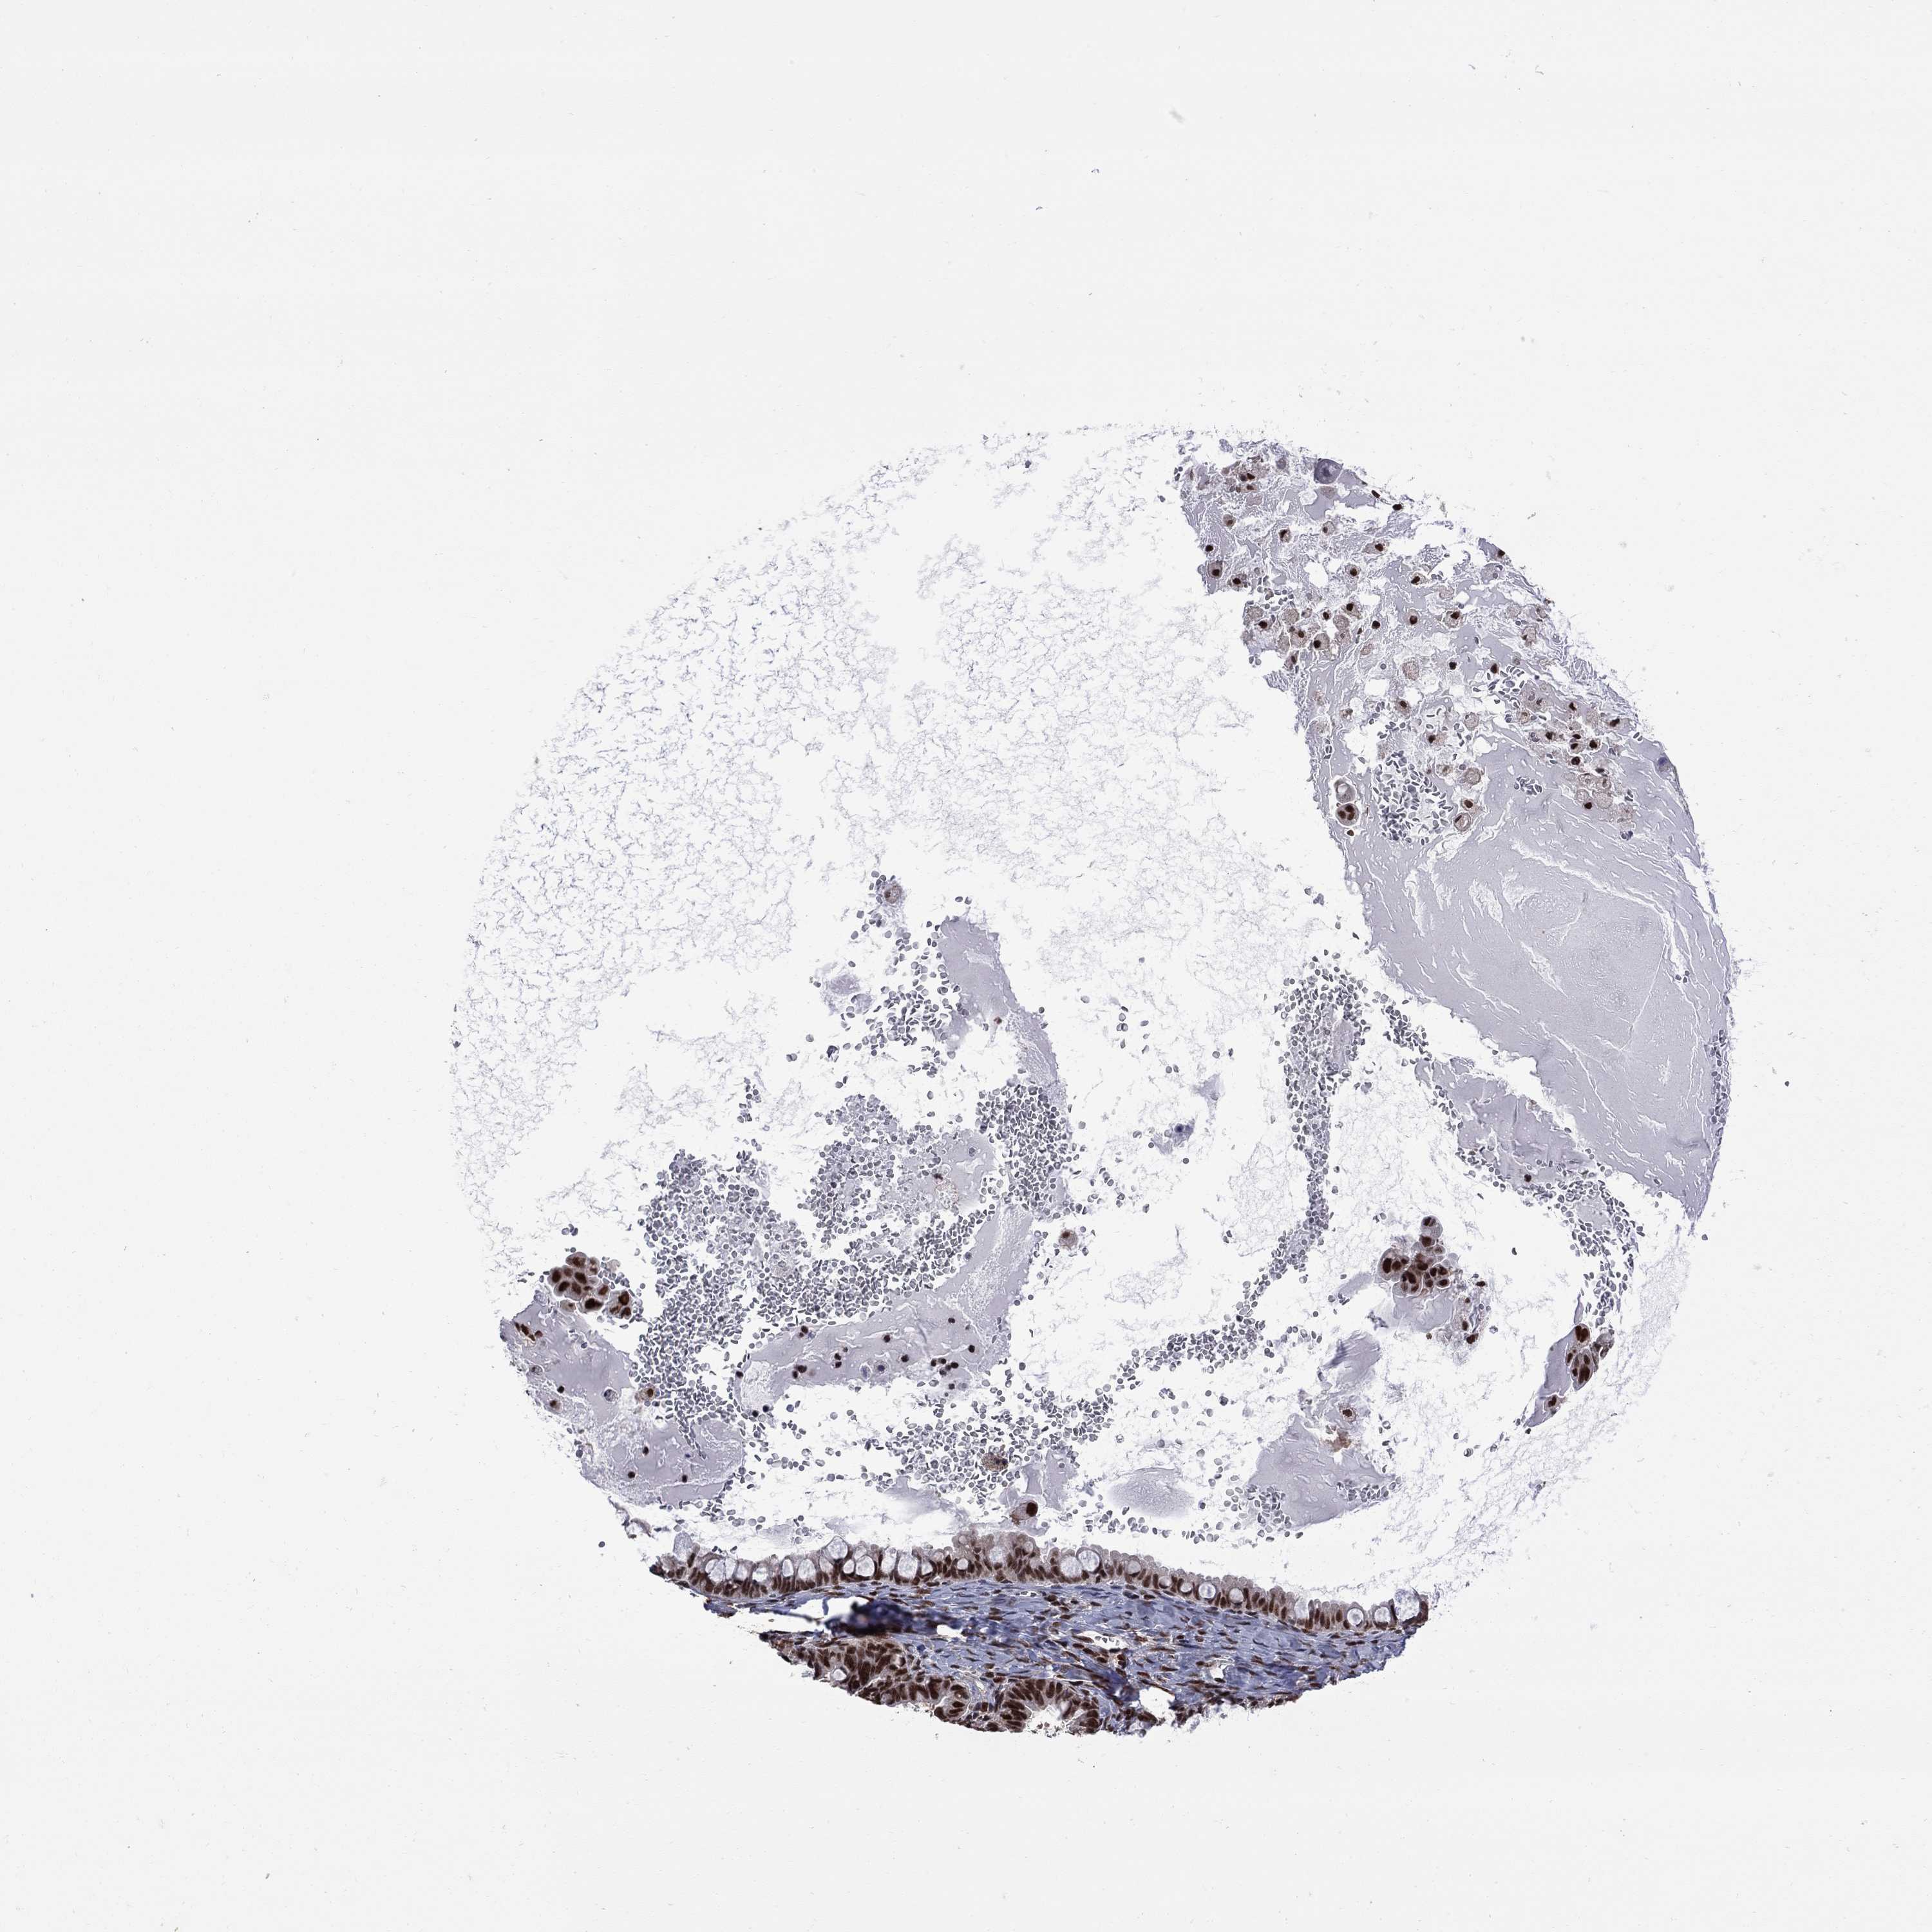

OVARIAN CANCER - Protein expressioni

A mouse-over function shows sample information and annotation data. Click on an image to view it in a full screen mode. Samples can be filtered based on level of antibody staining by selecting one or several of the following categories: high, medium, low and not detected. The assay and annotation is described here.

Note that samples used for immunohistochemistry by the Human Protein Atlas do not correspond to samples in the TCGA dataset.

Antibody stainingi

Antibody staining in the annotated cell types in the current human tissue is reported as not detected, low, medium, or high, based on conventional immunohistochemistry profiling in selected tissues. This score is based on the combination of the staining intensity and fraction of stained cells.

Each image is clickable and will lead to virtual microscopy that enables deeper exploration of all samples and also displays staining intensity scores, fraction scores and subcellular localization as well as patient and tissue information for each sample.

Antibody HPA068802

Staining

High

Medium

Low

Not detected

Intensity

Strong

Moderate

Weak

Negative

Quantity

>75%

75%-25%

<25%

None

Location

Nuclear

Cytoplasmic/membranous

Cytoplasmic/membranous,nuclear

Cystadenocarcinoma, serous, NOS

Cystadenocarcinoma, mucinous, NOS

Carcinoma, endometroid